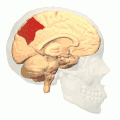

Precuneus of left cerebral hemisphere (shown in red).

Medial surface of left cerebral hemisphere. (Precuneus visible at top left.)- Medial surface of left cerebral hemisphere. (Precuneus colored in red.)